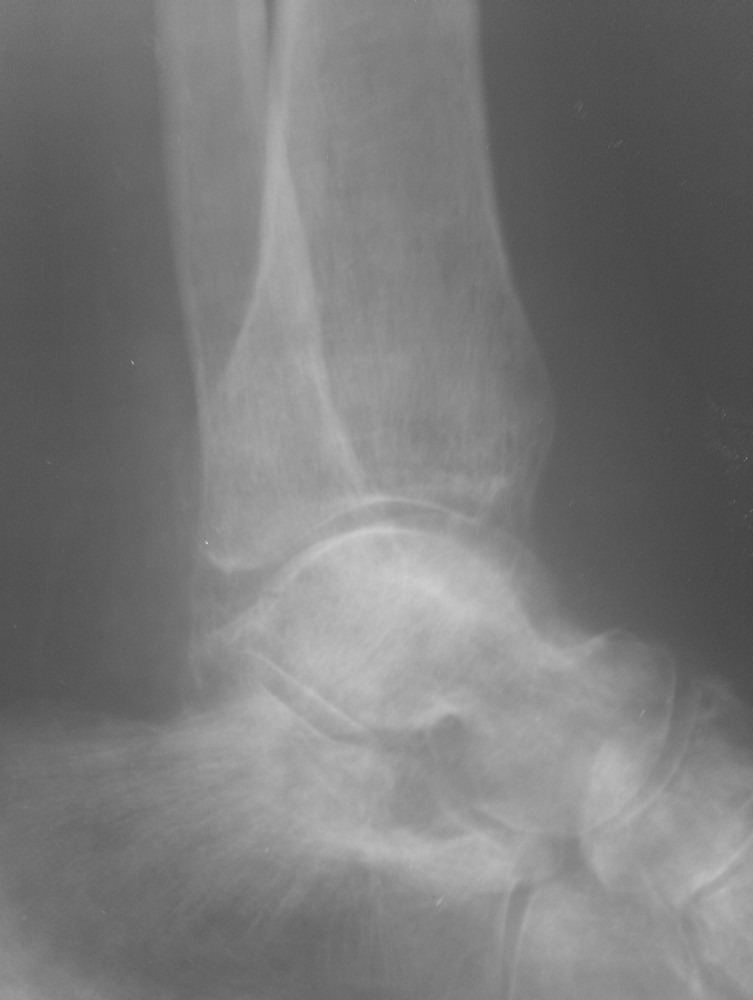

Травма от июля 2011 года, лечили консервативно гипсовым тутором (про травму лодыжек - не помнит или не знает). Через 2 недели после травмы - легочная эмболия и илеофеморальный тромбоз, находился на стац лечении. После теоретического сращения мыщелков и снятия гипсового тутора разработка движений безрезультативна, опорности конечности нет. Со слов - прыгает на костылях до самого настоящего момента.Сейчас - боль, передний ящик, люфт при нагрузке на ВБС. Боль в области внутренней лодыжки. Движения в голеностопе 5-0-15, в коленном суставе - 0-0-10, болезненные. При попытке встать полным весом и сделать шаг - нестабильность, ногу подворачивает.Ваши предложения?Пациент просит опорной ноги, сам вроде как активный (хотя толком объяснить, чем он занимался целый год, не может..)С Уважением, Останин

Неплохо было бы увидеть КТ мыщелков или рентгенограммы;) Что означает нестабильность при попытке сделать шаг? Передний ящик -сомнительно при таком объеме движений. Люфт и ногу подворачивает - а что люфтит? и куда он ее подворачивает (похоже больше чем на сгибание)? Если речь идет о вальгусном отклонении, то следует разделить: вальгус от импрессии, вальгус от боковой связочной нестабильности или повреждено и то и другое? Не совсем понятно где болевой синдром более выраженный? Если больной не может понять где болит больше - я бы шел от переферии к центру (плюс к тому, на моем нечетком мониторе голеностоп выглядит хуже).